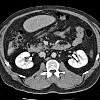

MRI of abdominal organs.

МРТ брюшной полости и забрюшинного пространства. Техника неинвазивной визуализации внутренних органов брюшины и забрюшинного пространства. В отличие от КТ и рентгеновских лучей, МРТ не поддерживает облучение, а воздействие на организм достигается внешним магнитным полем. Исследование этой области может включать МРТ печени, желчных протоков, поджелудочной железы, кишечника, мочевыделительной системы, надпочечников, брыжеечных сосудов, тщательное изучение структур брюшной полости. Диагностические возможности исследования чрезвычайно широки - это выявление пророков развития, воспалительных заболеваний, ран, органических поражений, источника кровотечений из желудочно-кишечного тракта, холедохолитиаза и стриктур желчных путей.

МРТ брюшной полости. Неинвазивная диагностическая процедура, основанная на получении информации путем декодирования радиомагнитных импульсов, излучаемых атомными ядрами во внешнем магнитном поле. Это позволяет создавать трехмерные изображения паренхиматозных и полых органов, лимфатических узлов, кровеносных и лимфатических сосудов. Используется для оценки размеров и формы внутренних органов, определения локализации, распространенности и типа патологических процессов.